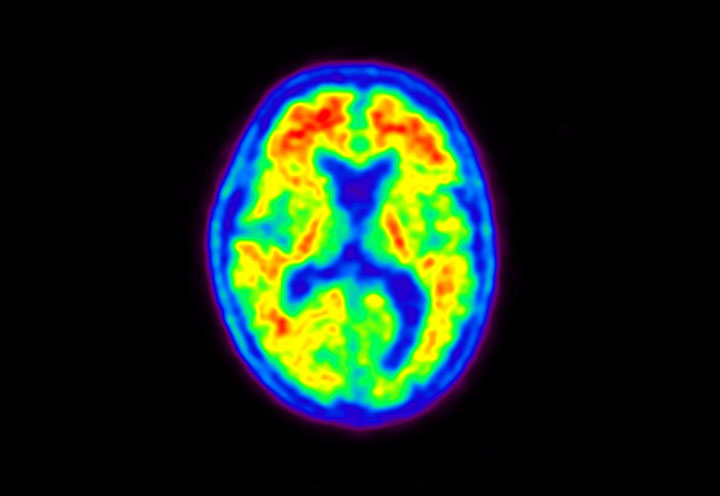

Head / Case5 : Amyloid

Coronal

Courtesy : Kindai University Hospital

- Imaging protocol

- Injected dose: 4.27 MBq/kg, 18F-Flutemetamol

- Uptake time: 99 minutes

- Scan time: 20 minutes